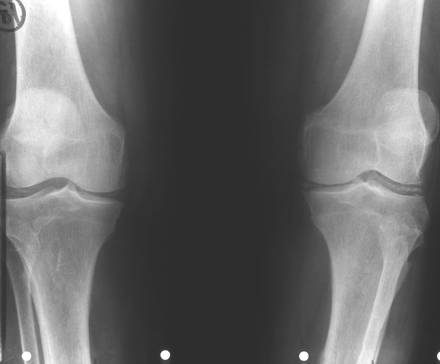

Fig. 84 – Tumora cu mieloplaxe

b)   Tumora cu mieloplaxe (celule gigante) – se intalneste exclusiv la adulti, afectand mai ales femeile. Are sediu epifizar, predilect langa genunchi si realizeaza o imagine transparenta, excentrica ce umfla osul. Imaginea descrisa are o structura neomogena data de travee opace ce dau un aspect de fagure tumorii. Corticala este impinsa in afara si subtiata. Trecerea intre tumora si diafiza sanatoasa are loc brusc, dand compactei un aspect amputat